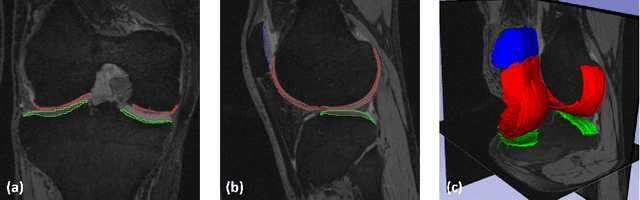

Abstract:The 3D morphology and quantitative assessment of knee articular cartilages (i.e., femoral, tibial, and patellar cartilage) in magnetic resonance (MR) imaging is of great importance for knee radiographic osteoarthritis (OA) diagnostic decision making. However, effective and efficient delineation of all the knee articular cartilages in large-sized and high-resolution 3D MR knee data is still an open challenge. In this paper, we propose a novel framework to solve the MR knee cartilage segmentation task. The key contribution is the adversarial learning based collaborative multi-agent segmentation network. In the proposed network, we use three parallel segmentation agents to label cartilages in their respective region of interest (ROI), and then fuse the three cartilages by a novel ROI-fusion layer. The collaborative learning is driven by an adversarial sub-network. The ROI-fusion layer not only fuses the individual cartilages from multiple agents, but also backpropagates the training loss from the adversarial sub-network to each agent to enable joint learning of shape and spatial constraints. Extensive evaluations are conducted on a dataset including hundreds of MR knee volumes with diverse populations, and the proposed method shows superior performance.